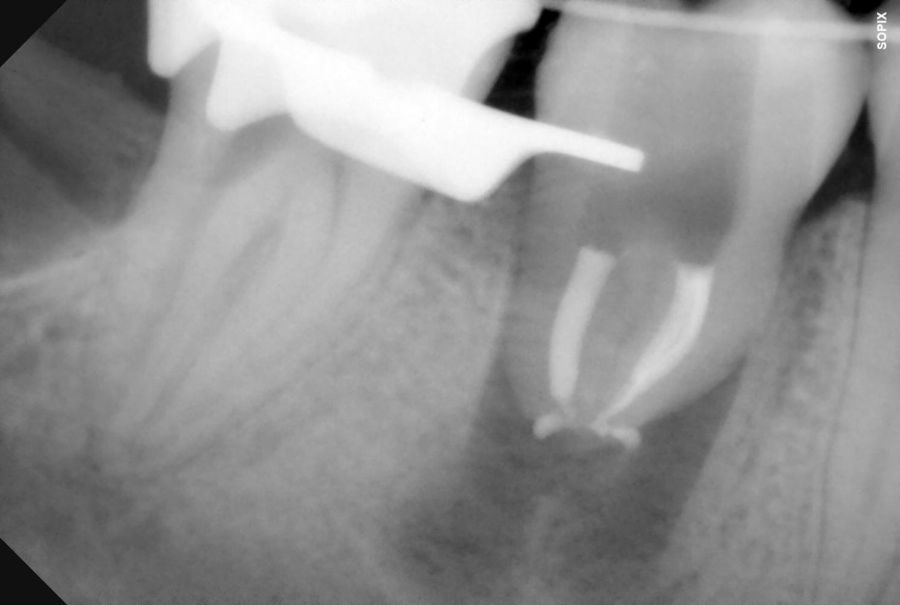

El autotrasplante dental es una opción terapéutica para aquellos casos en la que una pérdida dentaria es reemplazada por un diente donante del mismo paciente. Este autotransplante colocado en el alveolo puede ser inmediato o diferido. Suele estar indicado en paciente joven, siendo más frecuente el autotransplante de cordal a primer o segundo molar, y el de premolar a incisivo. El diente donante debe reunir unos criterios clínicos que aumenten el éxito de la técnica, basados en la morfología, el estadio de desarrollo radicular y la salud periodontal. La planificación se llevará a cabo con un CBCT y simulación virtual que genere un prototipo réplica en 3D; esto permite evaluar las dimensiones del diente donante para su correcta colocación en el alveolo receptor.

Se reporta el caso de un autotrasplante del tercer molar inferior derecho al alveolo postextracción de un primer molar inferior, en una paciente de 22 años de edad. Actualmente, el autotransplante se considera una opción de tratamiento si se siguen los criterios de selección del caso adecuados, y se realiza una técnica quirúrgica protocolizada. El diagnóstico planificado mediante CBCT, la simulación virtual y la confección de una réplica en 3D optimiza la técnica de forma segura, predecible con tiempos de cirugía menores.

El sitio receptor debe garantizar la adaptación del diente donante, se realizará un diagnóstico mediante planificación con CBCT que permita segmentar virtualmente el diente donante y llevarlo digitalmente al sitio receptor3.

En la revisión sistemática realizada por Barrientos y cols.10, se analizan puntos clave para el protocolo de AD, como los diferentes materiales de fijación del autotrasplante, alambre, resina, sutura, fijación ortodóntica o férulas acrílicas. La tasa de éxito del procedimiento varían entre un 76% y un 95%. La necesidad del tratamiento de conductos, en el 21,1% de dientes no se realizó endodoncia, principalmente en casos con ápice abierto y la tasa de éxito fue más alta cuando la endodoncia se efectuó alrededor del primer mes postoperatorio (en dos semanas: 95,75%; de 7 días a 4 semanas: 90%, y de 6 días a 4 semanas 92,5%. En cuanto a la supervivencia de los dientes trasplantados se apreció que la tasa de éxito disminuye con el paso del tiempo (más de siete años 84%).10.